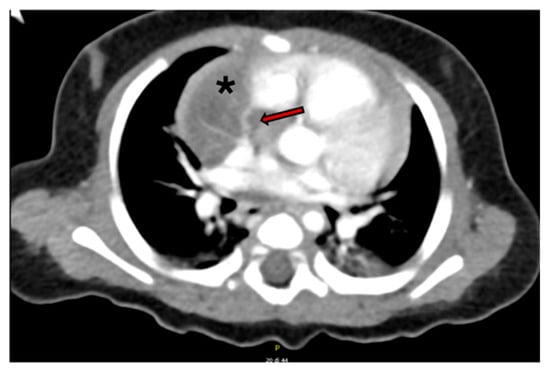

Intrapericardial Extralobar Pulmonary Sequestration: A Case Report and Systematic Review of a Unique Embryologic Variant

Background: Intrapericardial extralobar pulmonary sequestration (ELPS) is an exceptionally rare congenital malformation. The location may mimic neoplastic lesions and poses diagnostic and surgical challenges. We present a new case and a systematic review of the literature. Case Presentation: A 3-month-old male infant was referred for evaluation of a congenital intrathoracic mass suspected to be an extralobar sequestration. However, intrapericardial location was not recognized. MRI and CT demonstrated a circumscribed lesion with arterial supply from the right pulmonary artery. Thoracoscopic exploration was attempted but converted to sternotomy. The mass was excised en bloc. Histopathological analysis confirmed extralobar pulmonary sequestration with cystic components, consistent with a hybrid lesion. Postoperative recovery was uneventful. Methods: A systematic literature review was conducted according to PRISMA guidelines across PubMed, Scopus and Embase databases, including only histologically confirmed intrapericardial ELPS. Results: Ten cases were identified. Including the present case, eleven cases have been reported. Prenatal detection occurred in 54% of cases. Fetal demise occurred in two cases due to cardiac tamponade. Aberrant arterial supply originated from the pulmonary arteries in 54% of patients and venous drainage into the right atrium or superior vena cava in 45%. Surgery via sternotomy was performed in all cases with excellent outcomes. Conclusions: Intrapericardial ELPS is an exceptionally rare but surgically curable entity. Early recognition and complete resection are essential to prevent life-threatening complications. This systematic review highlights a consistent vascular pattern supporting its classification as a unique embryologic variant within the CPAM–sequestration spectrum. Full article

Figure 1